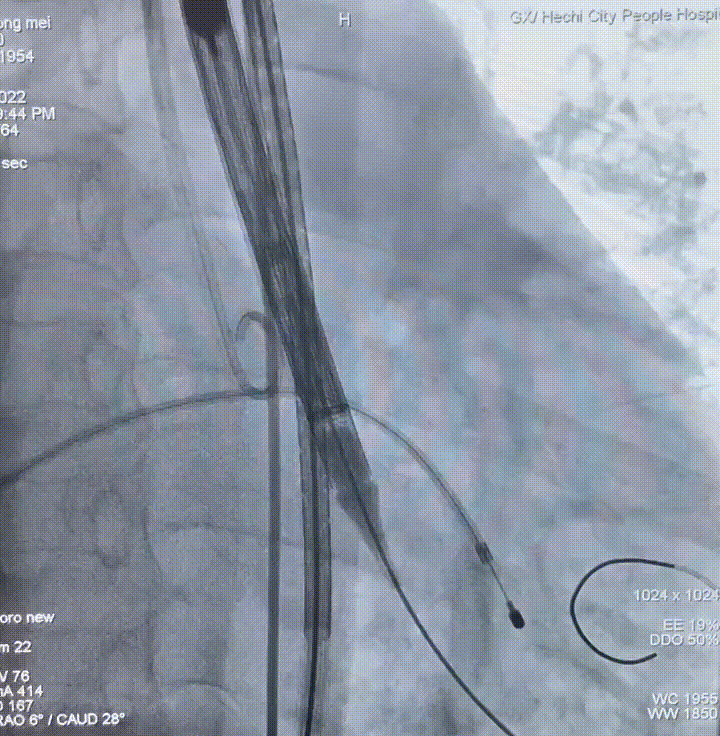

瓣膜定位

瓣膜释放